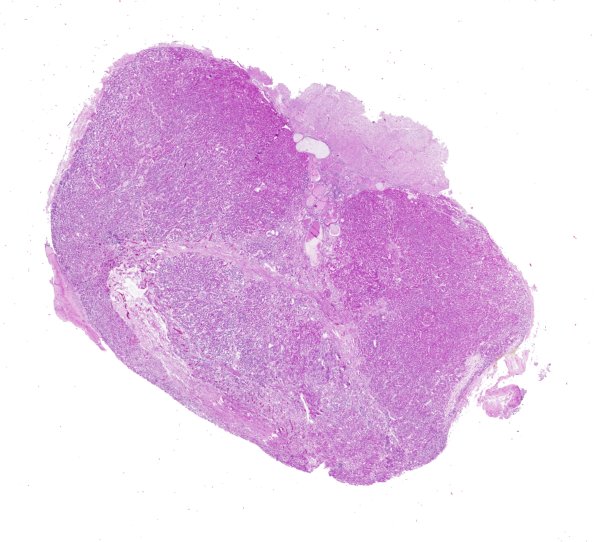

Washington University Experience | NORMAL | Pituitary gland | 4B1 Pituitary, normal H&E whole mount

4B,C Subpopulations of pituitary adenohypophysis cells are typically identified currently by immunohistochemistry of hormones and transcription factors; however, in days gone by special histochemical stains were used to identify populations of cells. ---- 4B1 This is a routinely stained adenohypophysis, the starting point for the subsequent stains. (H&E)